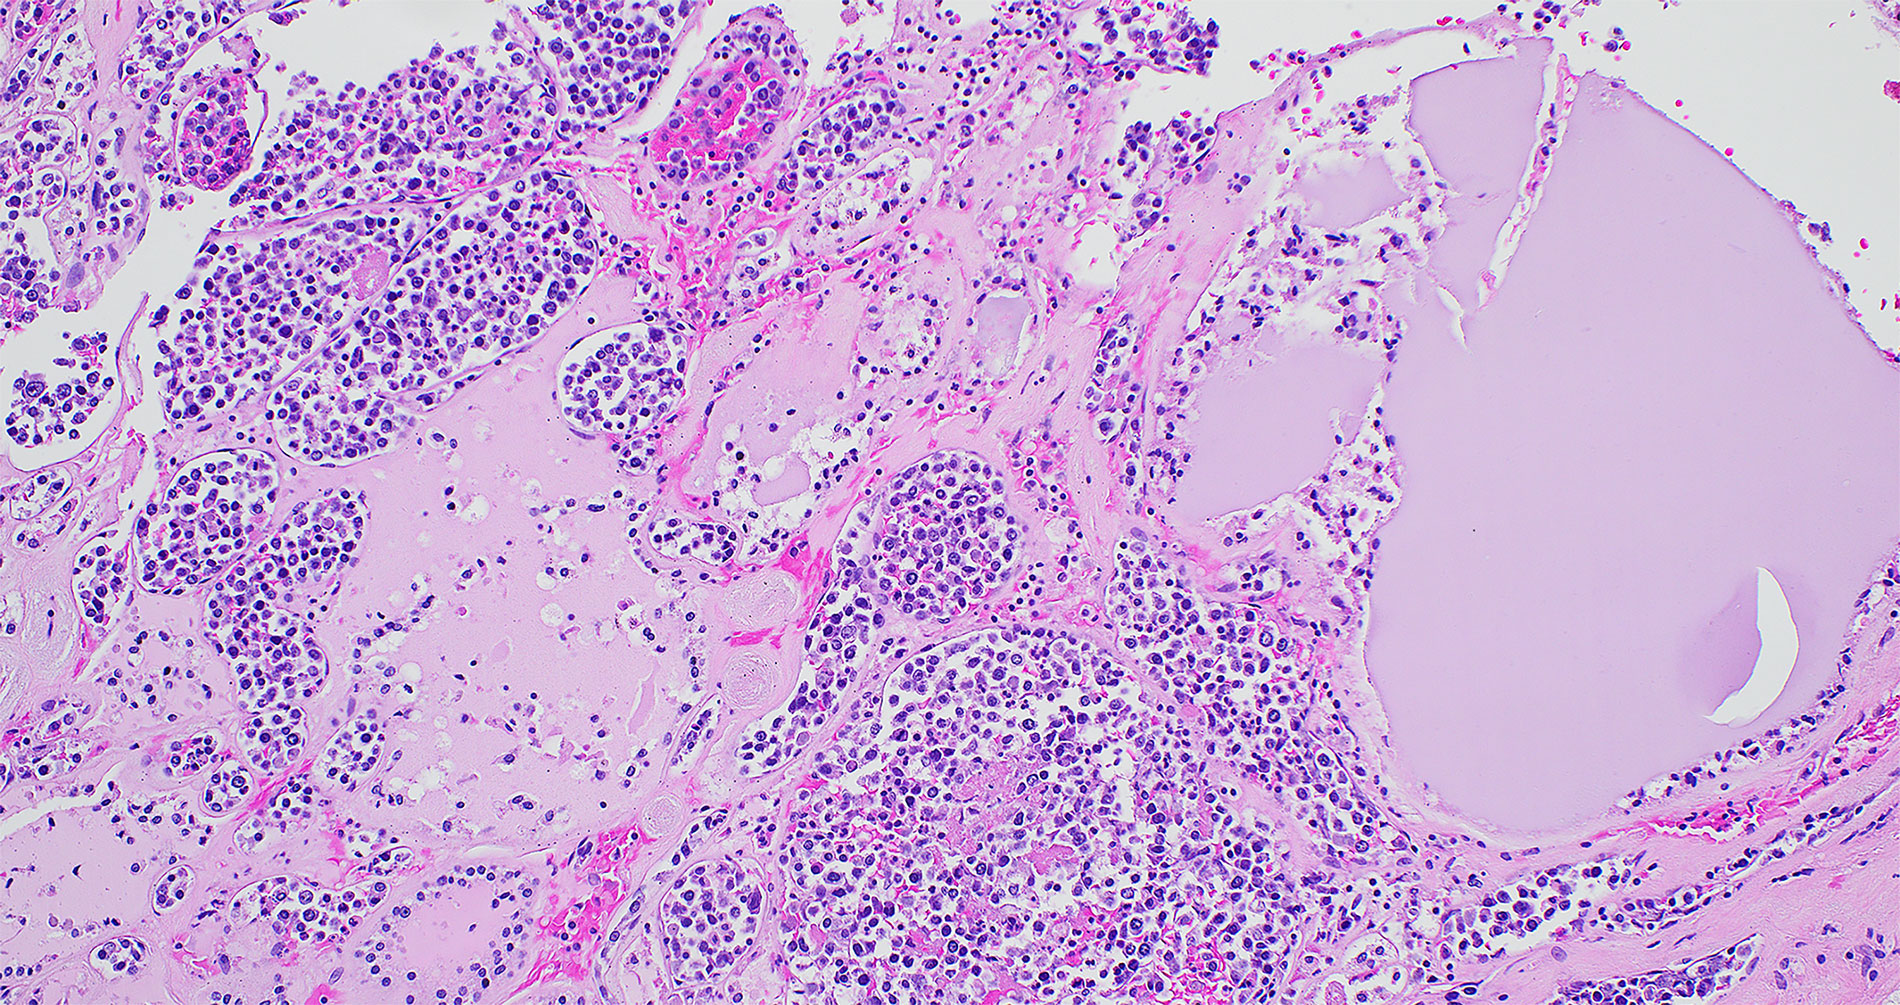

Case 72: An Elderly Male with Multi-Organ Failure

An elderly man presented with progressive neurologic decline in the setting of stroke. Laboratory results showed a normal white blood cell count (7k/uL), severe anemia (hemoglobin 6.6 g/dL), and thrombocytopenia (platelets 104k/uL). The patient’s condition worsened over the span of a couple of weeks with multiple organ failure, and he passed away shortly after.